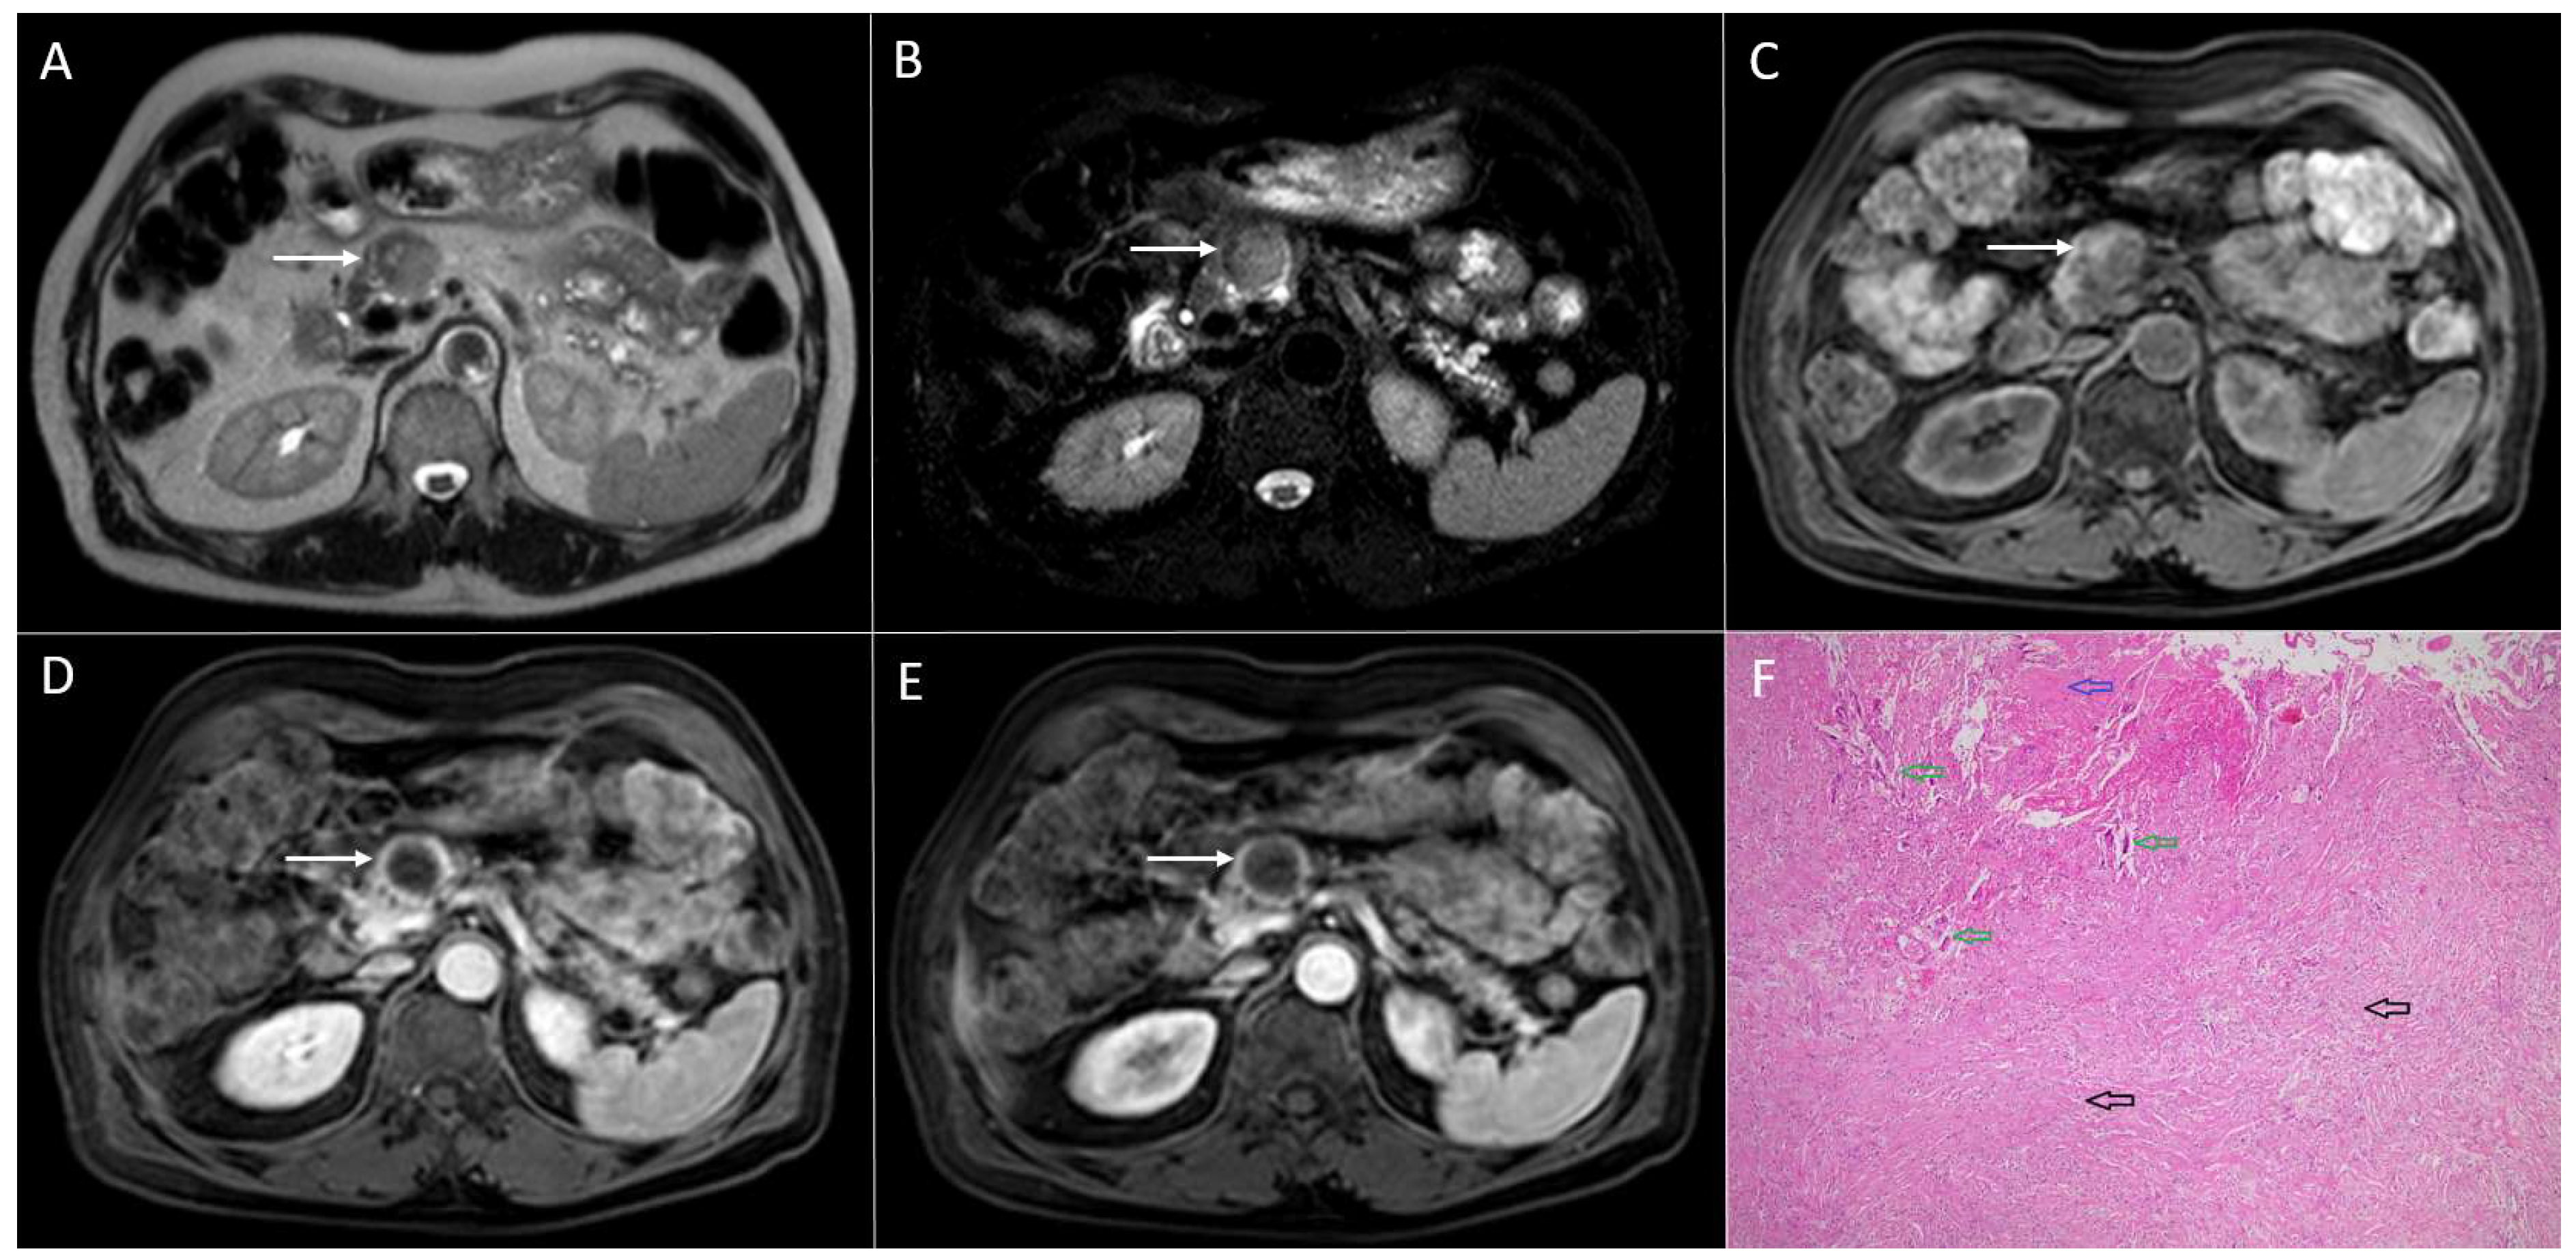

3.1. Neuroendocrine Tumors